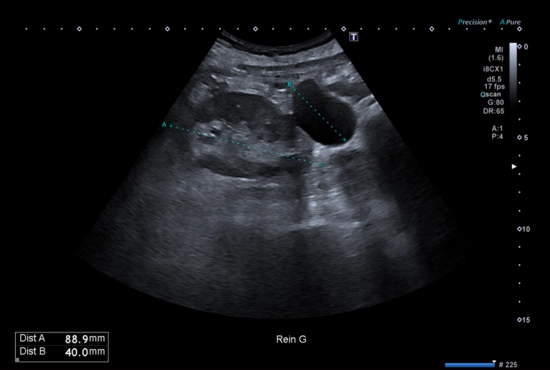

Echographie de la face antérieure de la cheville

24/12/2025